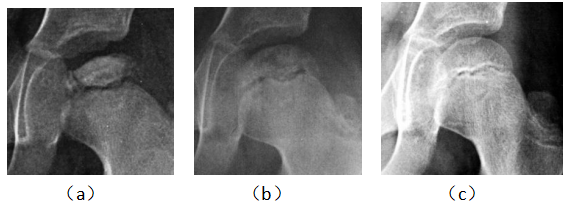

病例1男,29岁,患病2年,治疗15个月痊愈。治疗前,股骨头顶部塌陷、变平,顶部可见大块坏死骨,密度增高(a)。经过9个月的治疗,死骨与正常骨融合,密度减低,表面不清楚(b)。治疗后,股骨头略平,骨密度均匀,骨小梁清晰(c)

Case 1 male, 29 years old, 2 years sick, 15 months after eating. Before eating, the top of the femoral head collapsed, flattened, the top of the large dead bone, increased density, uneven thickness (a). After 9 months of treatment, the dead bone fused with the normal bone, the density decreased and the surface was unclear (b). After eating, the femoral head is slightly flat, the bone density is even, and the bone trabecula is clear (c).

病例2,66岁,患病8年,治愈16个月修复。治疗前股骨头平坦,关节面粗糙,间隙消失,密度不均,有椭圆形死骨量(a)。进食后,关节间隙出现,关节表面光滑,骨密度恢复(b)

Case 2, 66 years old, 8 years sick, 16 months cured. Before eating, the femoral head was flat, the articular surface was rough, the space disappeared, the density was uneven, there were oval dead bone mass (a). After eating, the joint space appeared, the joint surface was smooth, and the bone density recovered (b)